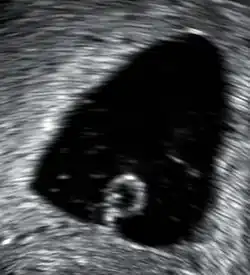

An anembryonic pregnancy (also called an "empty sac" or "blighted ovum") is a condition where the gestational sac develops normally, while the embryonic part of the pregnancy is either absent or stops growing very early. This accounts for approximately half of miscarriages. All other miscarriages are classified as embryonic miscarriages, meaning that there is an embryo present in the gestational sac. Half of embryonic miscarriages have aneuploidy (an abnormal number of chromosomes).[60]